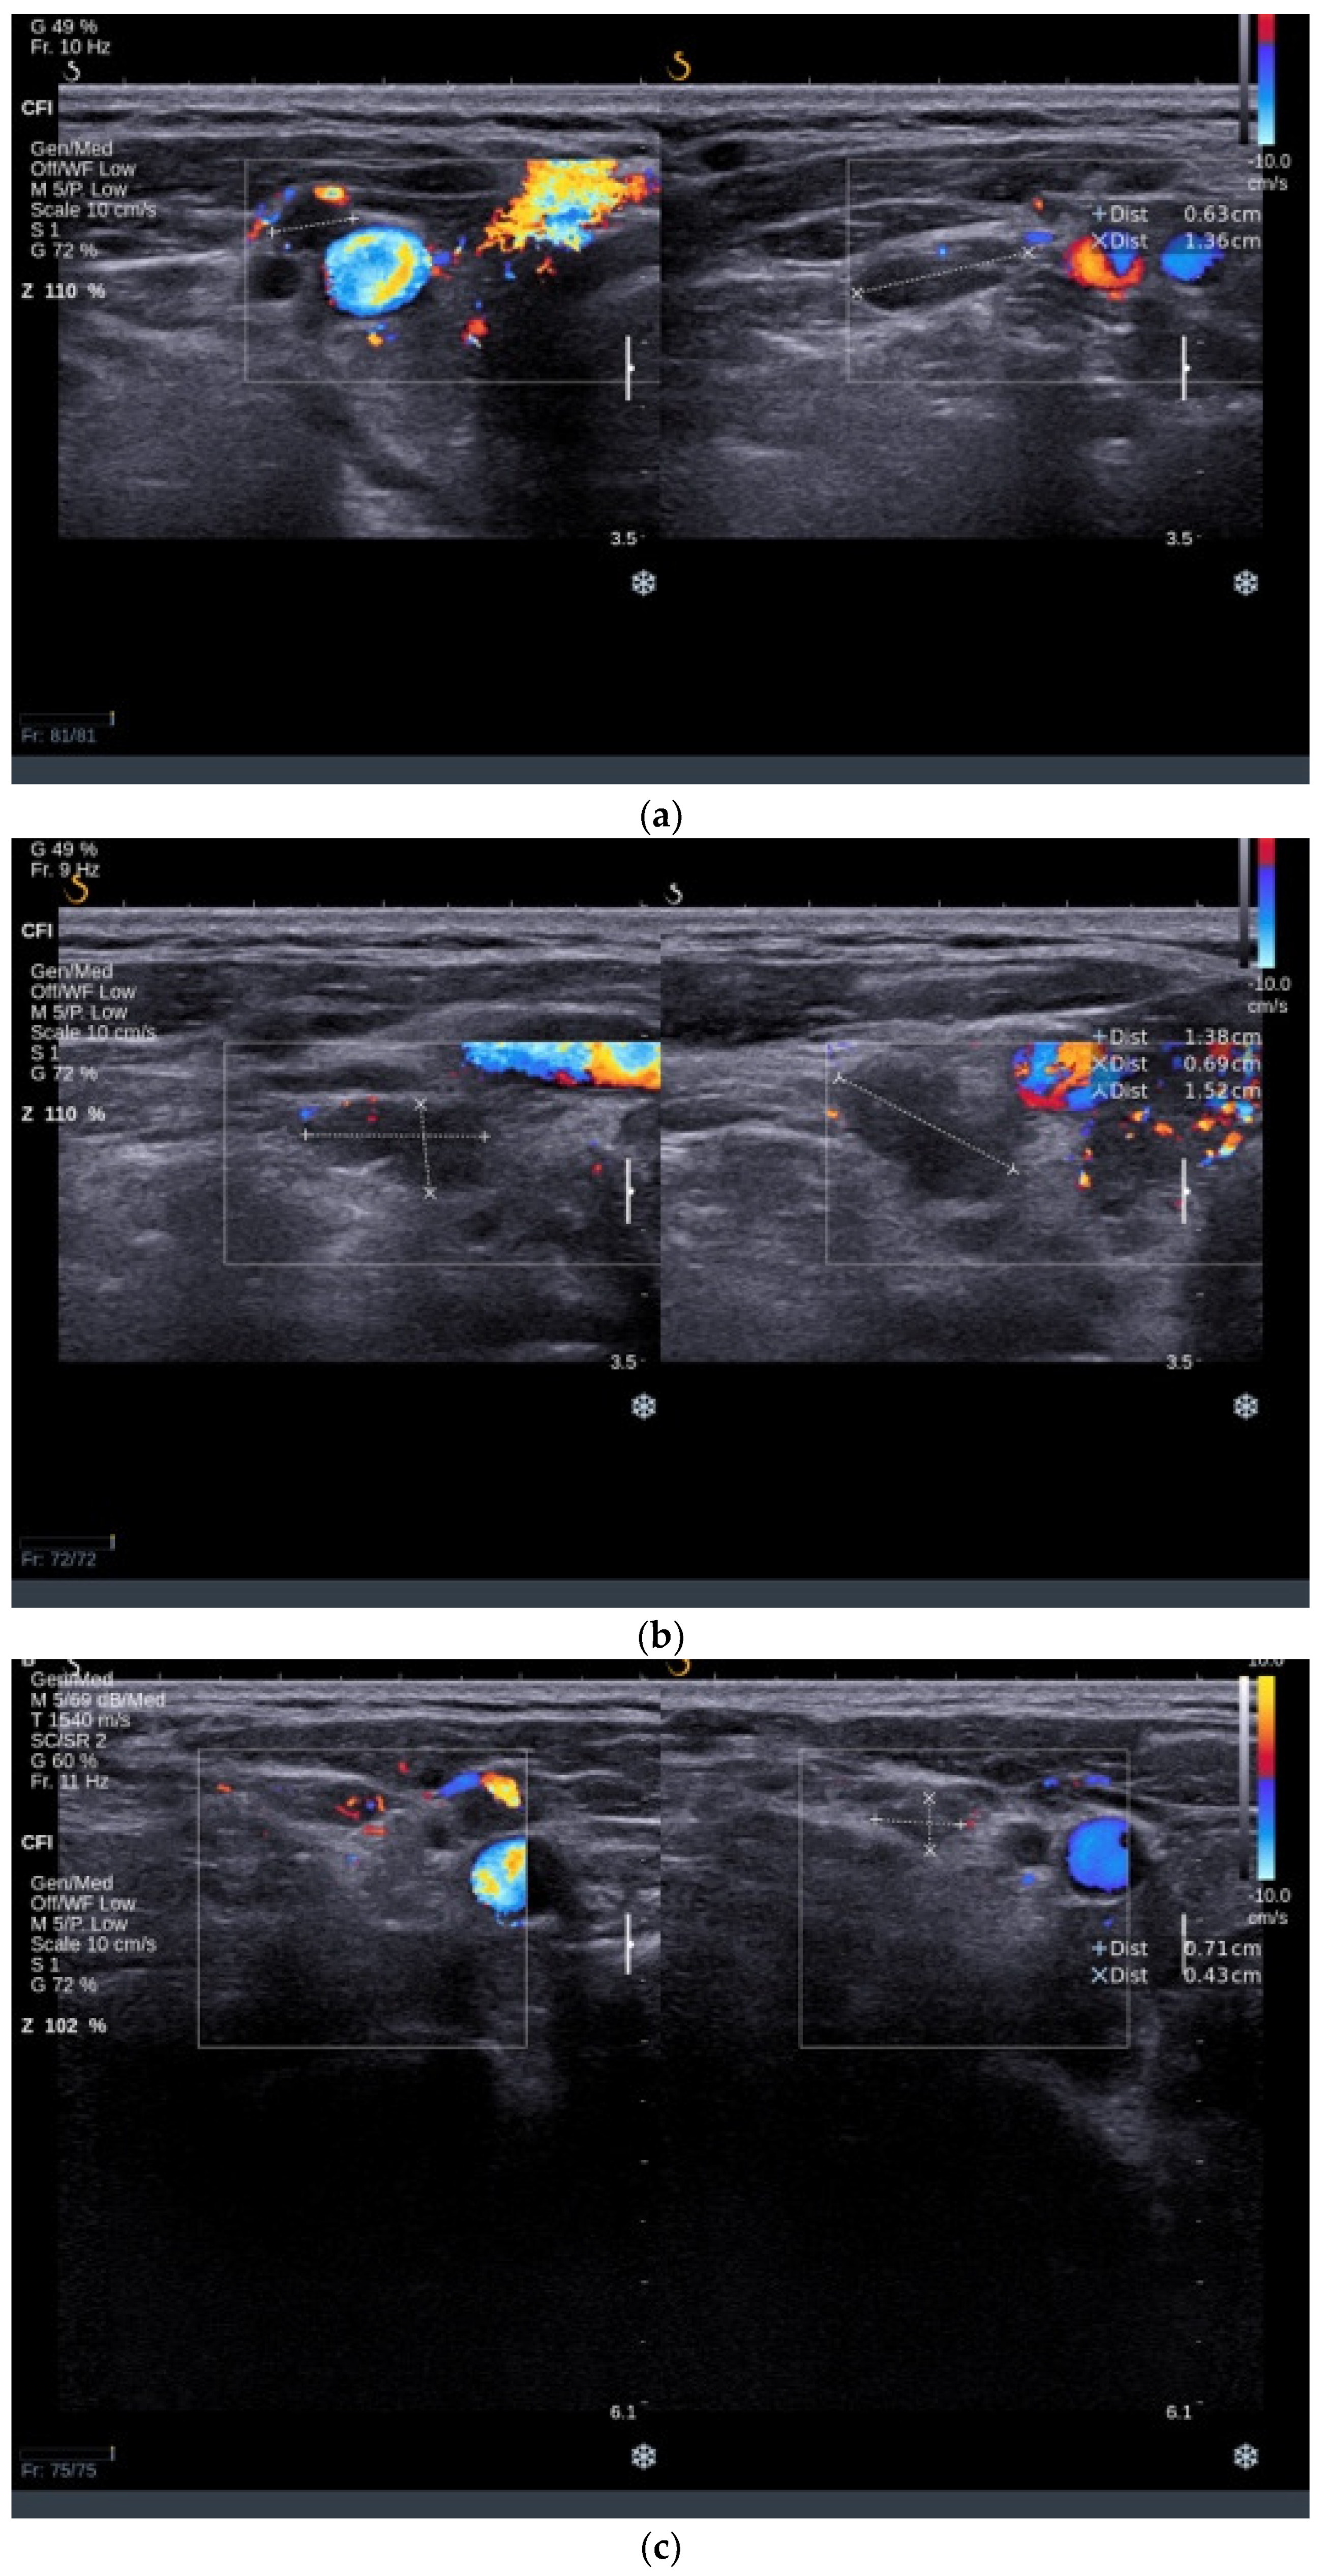

3.1.2. Thyroid Ultrasound

3.2.2. Thyroid Ultrasound

3.3.2. Thyroid Ultrasound